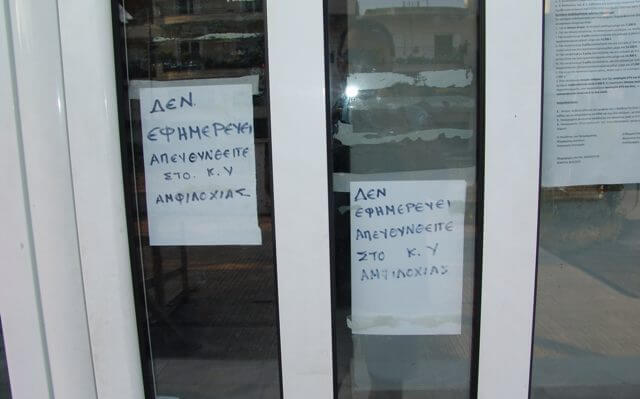

Ο άδικος θάνατος πρόωρου βρέφους στην Τήνο έφερε για μια ακόμη φορά στην επιφάνεια τις τραγικές ελλείψεις του υγειονομικού συστήματος. Κυρίως στη νησιωτική χώρα, όπου οι κάτοικοι παίζουν τη ζωή τους κορώνα γράμματα καθημερινά εξαιτίας της ανεπάρκειας μέσων και κατάλληλης υγειονομικής περίθαλψης.